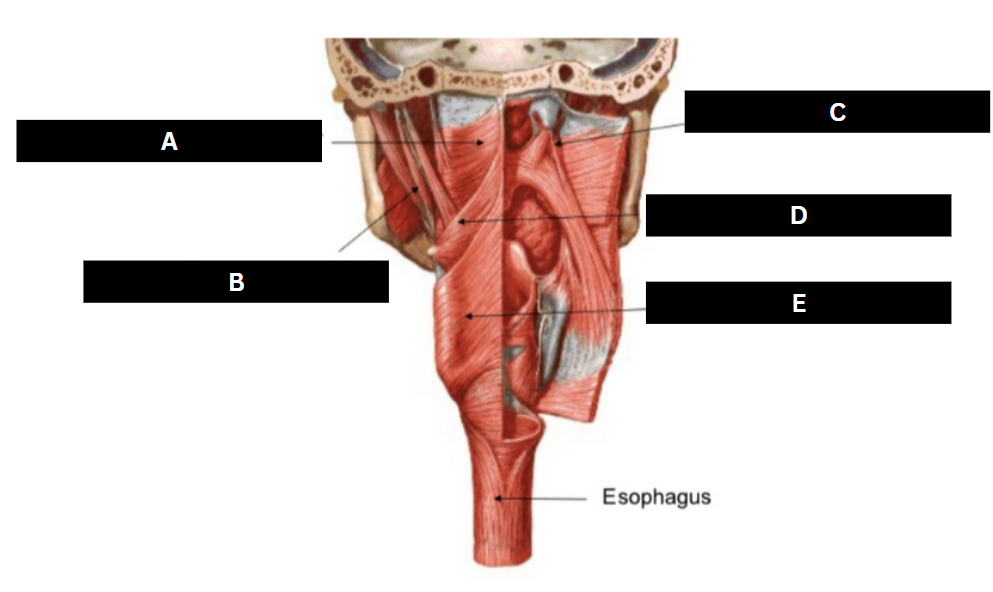

Superior pharyngeal constrictor

origin is on the pterygomandibular raphe, coursing posteriorly to insert on the median raphe of the pharyngeal aponeurosis function is to pull the pharyngeal wall forward to constrict the pharyngeal diameter

Middle pharyngeal constrictor

origin is on the horns of the hyoid and stylohyoid ligament, coursing up and back to the median pharyngeal raphe; function is to narrow the diameter of the pharynx

Inferior pharyngeal constrictor

origin is the oblique line of the thyroid laminae, coursing up and back to insert on the median pharyngeal raphe; function is to reduce the diameter of the lower pharynx

Cricopharyngeus

origin is the cricoid cartilage, coursing back to the orifice of the esophagus; function is to constrict the superior orifice of the esophagus; also referred to as the upper esophageal sphincter

Salpingopharyngeus

origin is the lower margin of the auditory tube, coursing down to insert into the palatopharyngeus muscle; function is to elevate the lateral pharyngeal wall

Stylopharyngeus

origin is the styloid process, coursing down to insert into the pharyngeal constrictors and the posterior thyroid cartilage; function is to elevate and open the pharynx

Superior Pharyngeal Constrictor

|  |  |

Middle Pharyngeal Constrictor

|  |  |

Inferior Pharyngeal Constrictor

|  |  |

Cricopharyngeus

|  |  |

Saplingopharyngeus

|  |  |

Stylopharyngeus

|  |  |

Superior pharyngeal constrictor

A

Stylopharyngeus

B

Salpingopharyngeus

C

Middle pharyngeal constrictor

D

Inferior pharyngeal constrictor

E